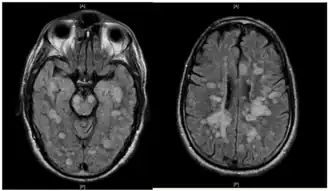

L'IRM cérébrale montre des lésions multifocales de la substance blanche :

- hypersignaux multiples en séquence T2 ou T2-FLAIR ;

- en signal T1, ces lésions fixent fortement le gadolinium[1] ;

- parfois un œdème périlésionnel ;

- parfois des lésions des noyaux gris centraux ou du thalamus.